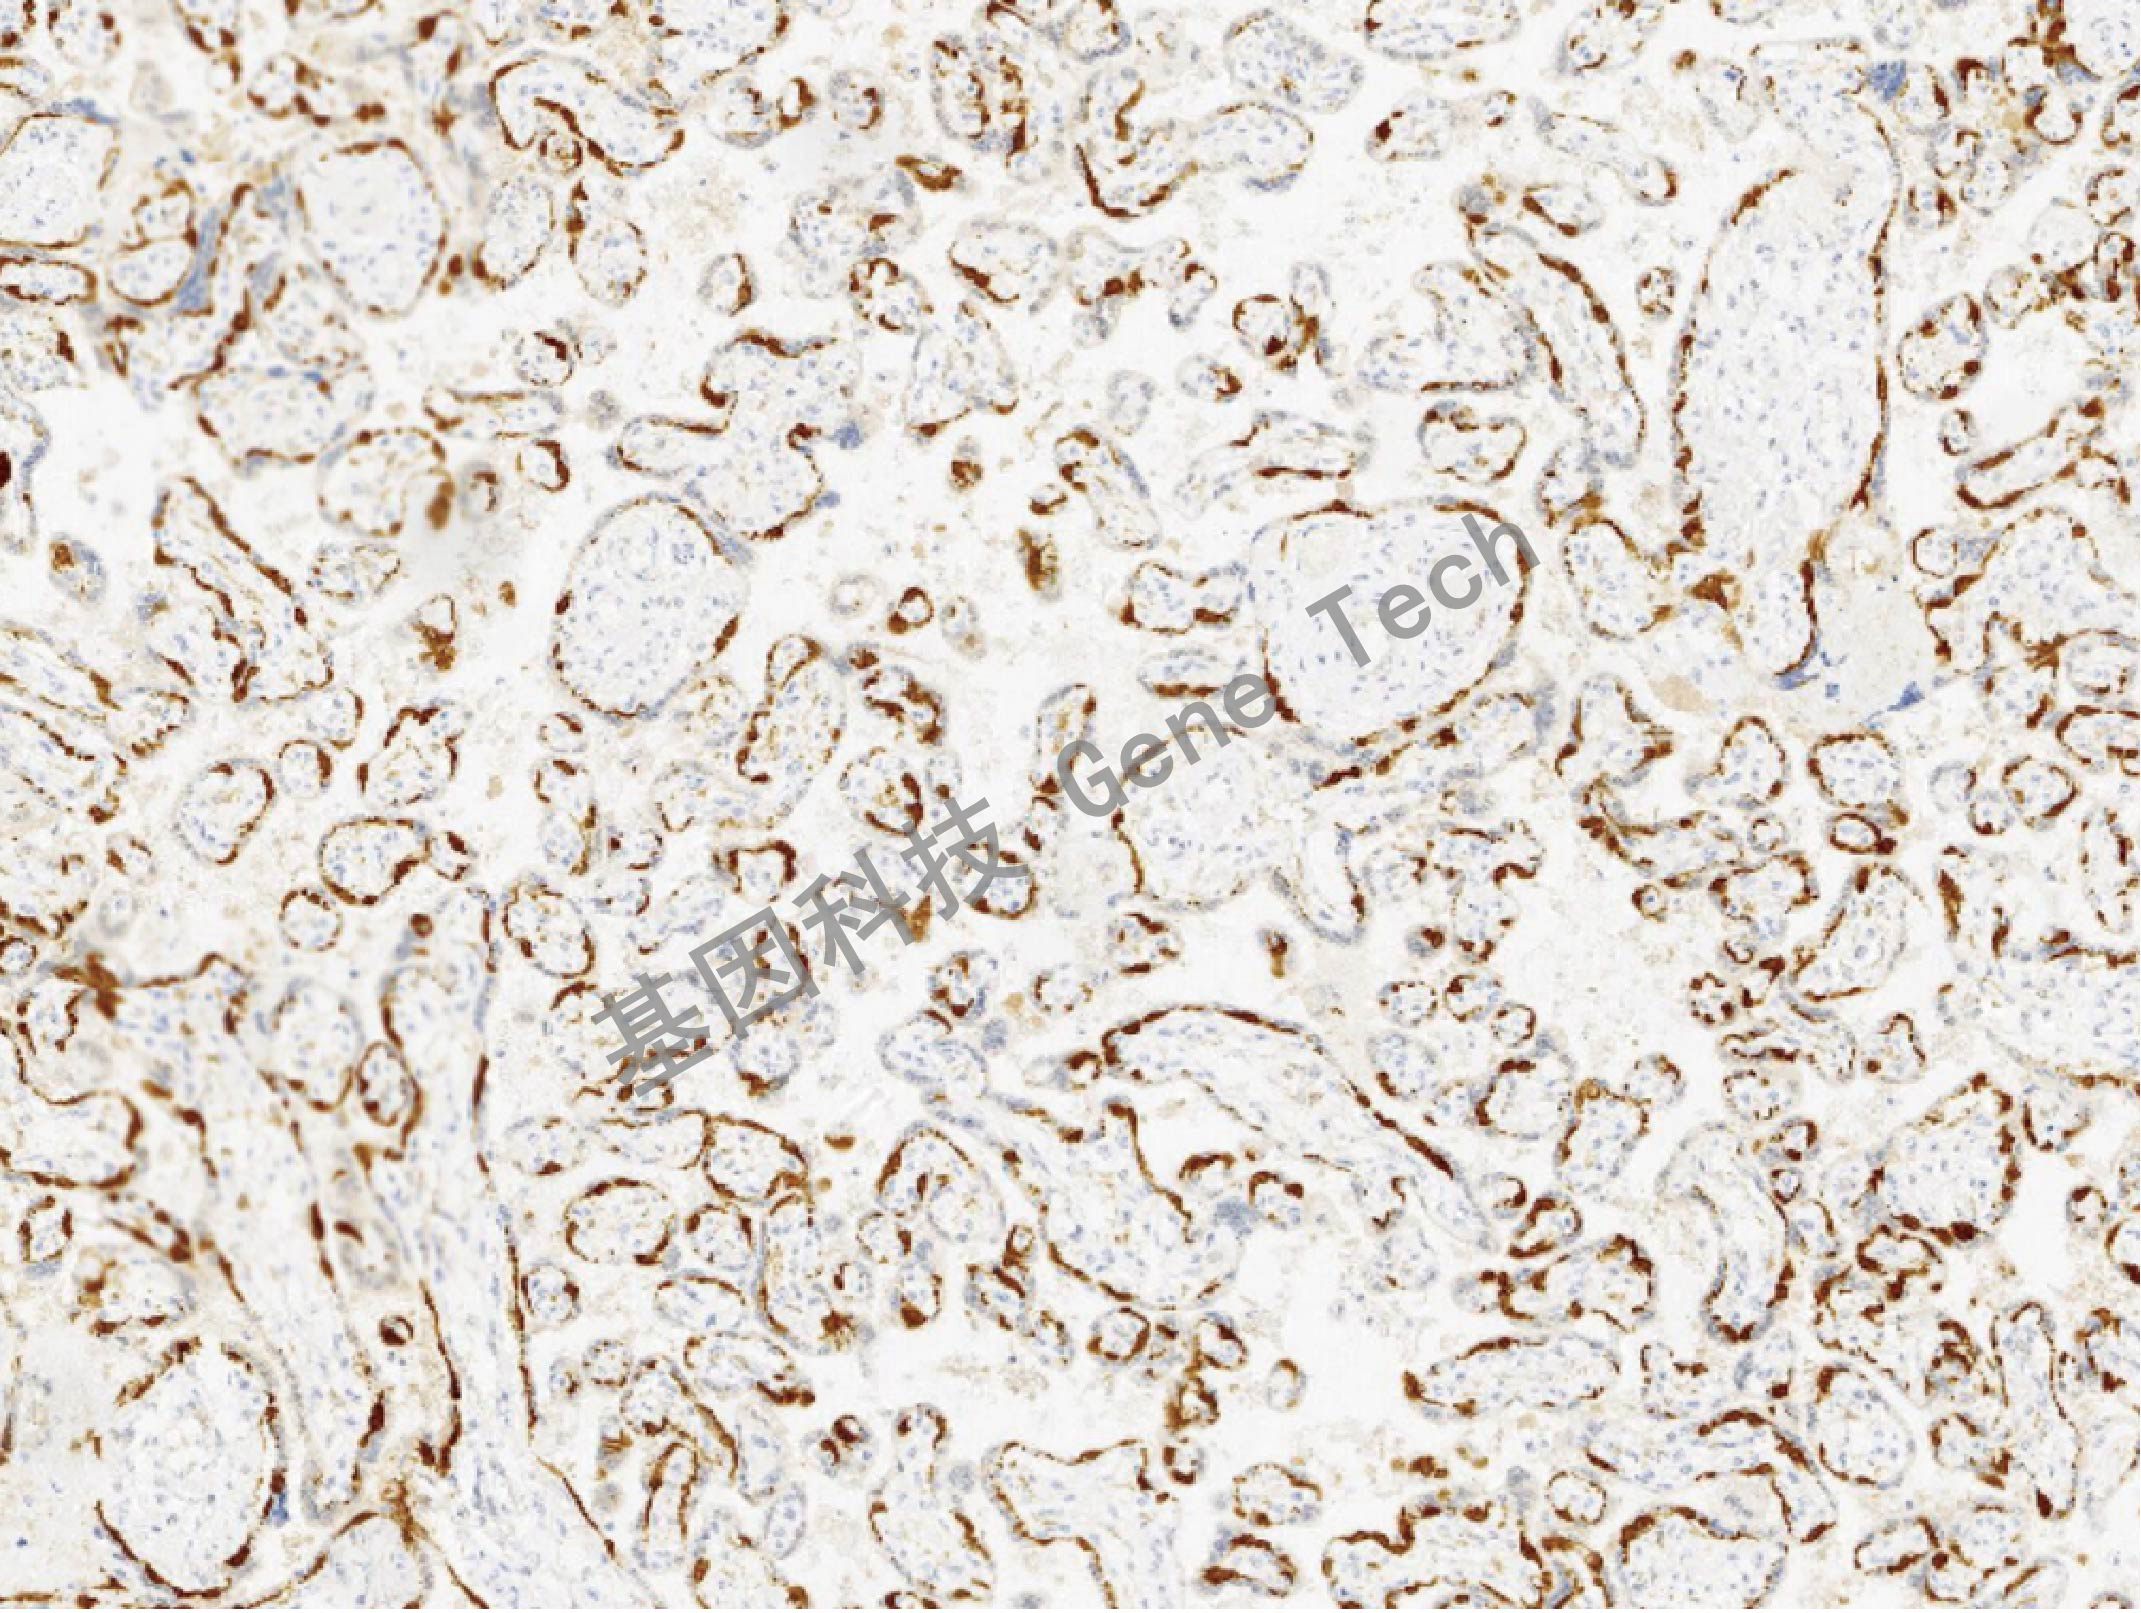

| 预处理:高pH热修复 | 阳性部位:细胞浆 | 阳性对照:胎盘 |

| 胎盘石蜡切片,用 PEG10(GT2418)染色,细胞浆阳性,DAB 显色。 | ||